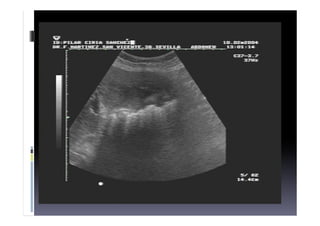

ECOGRAFIA

HEPATO-BILIO-PANCREATICA

Falsos Negativos

Pueden ser cálculos pigmentarios o de muy

pequeño tamaño que no muestran sombra

acústica posterior, por litiasis impactadas o por

vesículas contraídas

Falsos Positivos

Por gas interpuesto del duodeno

 Foto ecografia

Barro Biliar

La presencia de bilis espesa puede

manifestarse como barro biliar, con ecos de

bajo nivel sin sombra acústica posterior,

creando un nivel líquido-líquido y a veces

dando imágenes amorfas simulando tumores